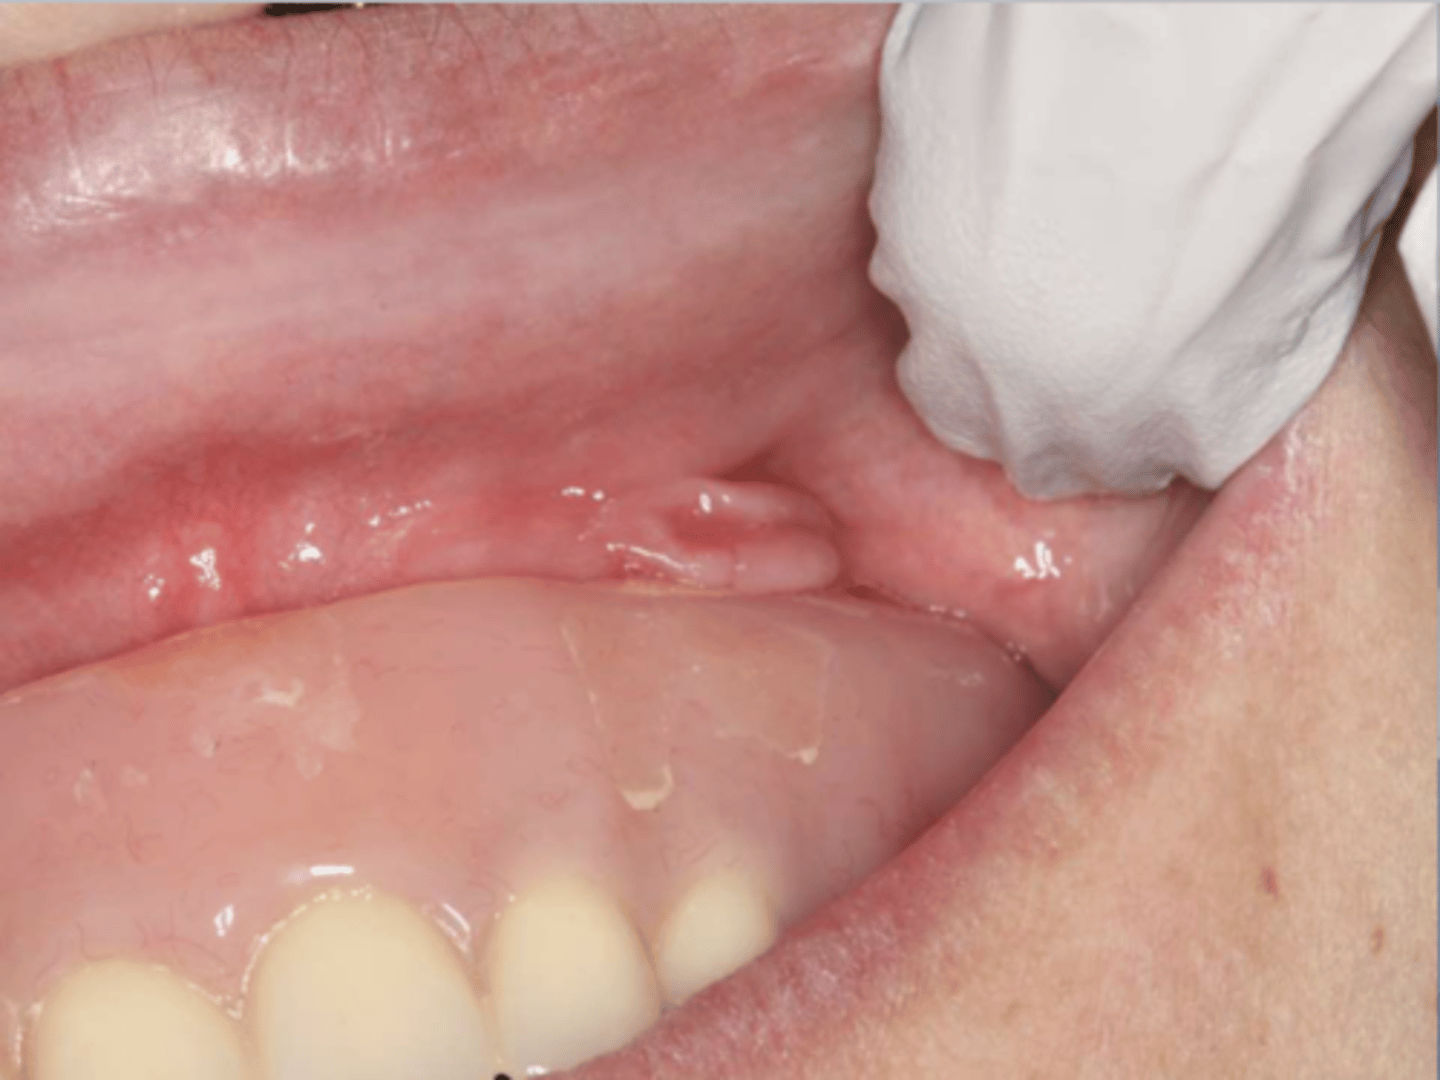

What do you suspect?

epulis fissuratum

Patient reported that their lower denture irritates their mouth. What do you suspect?

What do the following clinical features describe?

-single or multiple folds of hyperplastic tissue in alveolar vestibule

-fibroepithelial poly/leaf-like denture fibroma may be seen along palatal mucosa